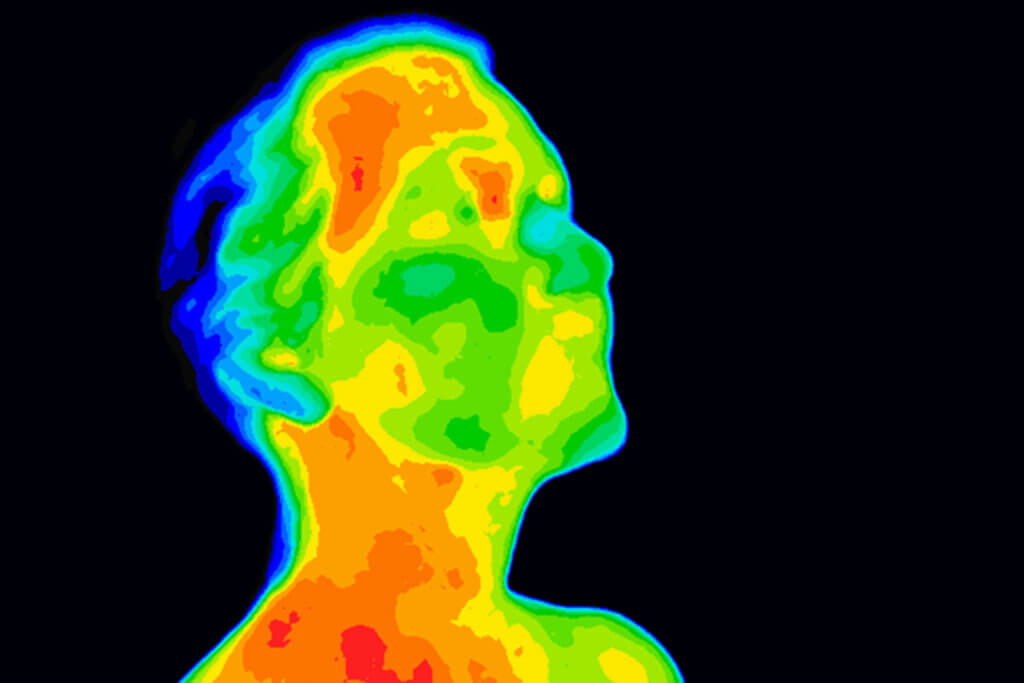

Wie eine gewöhnliche Digitalkamera erfasst die Wärmebildkamera kontaktlos ein Motiv und zeichnet es als Bild auf. Die Konturen des Motivs bleiben auch bei der Wärmebildkamera originalgetreu. Die Farben weichen jedoch ab, denn sie bedient sich einer Farbskala, um Temperaturen im Bild grafisch darzustellen. Meist beginnt die Wärmebildskala bei einem dunklen lila für extreme Kälte und endet bei einem dunklen rot für extreme Hitze. Die Wärmebildkamera erstellt also eine Thermografie (ein Wärmebild), die bildliche Darstellung unterschiedlicher Temperaturen.

Sogar im medizinischen Bereich ist der Einsatz von Wärmebildkameras sinnvoll. Entzündungsherde weisen eine erhöhte Temperatur auf, was ein Mediziner auf einem hochauflösenden und stark differenzierenden Wärmebild erkennt. Reihenuntersuchungen großer Menschenmengen auf Fieber, beispielsweise im Rahmen der Seuchenkontrolle am Flughafen, lassen sich dank Wärmebildkameras schnell und ökonomisch bewältigen.

Auf Durchblutungsstörungen andererseits weisen kühlere Bereiche hin. Der Ausgangspunkt einer solchen Störung lässt sich aufgrund des Wärmebildes leichter lokalisieren und die Ursache damit leichter diagnostizieren. Sogar bei der Erkennung von Brustkrebs spielt Thermografie eine bedeutende Rolle.